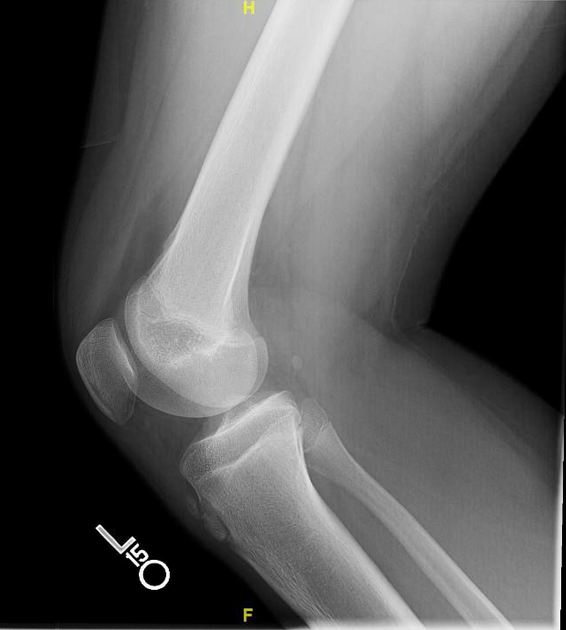

Puzzle 70

What's the Diagnosis?

Guess 1 / 5